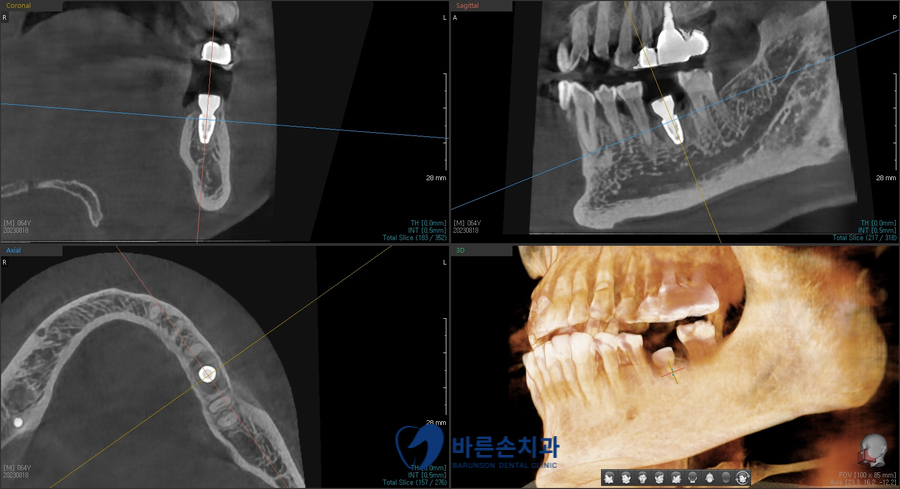

CT를 찍어서 확인한 결과,

발치와 동시에 임플란트가 가능한 상황이며,

약간의 뼈이식이 필요하다는 진단이 나왔습니다.

3차원 CT를 찍어 임플란트가 잘 심어졌는지 확인하고

수술을 마무리 합니다.